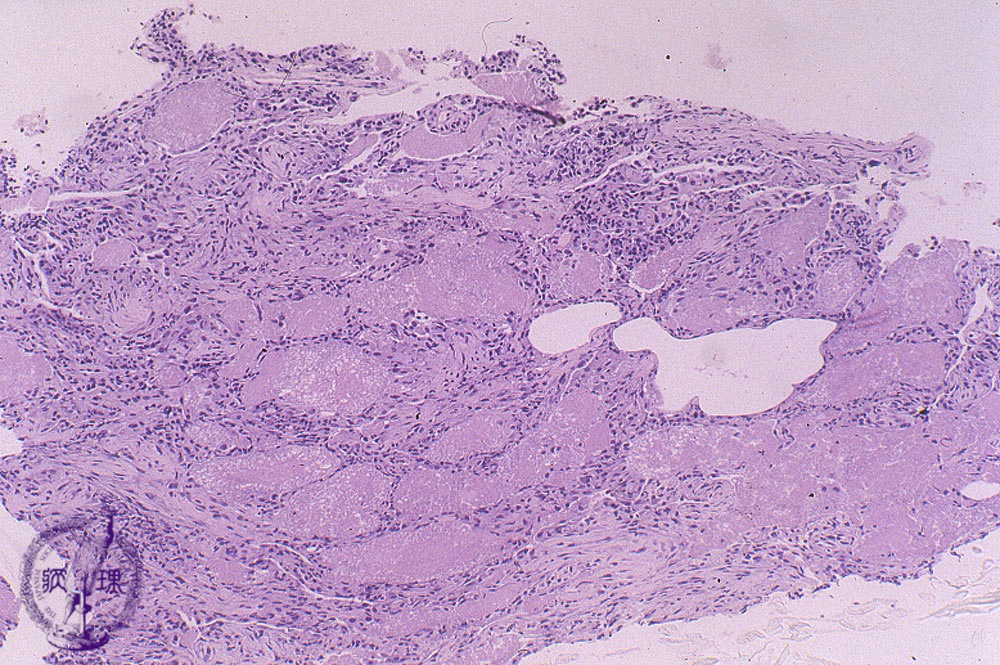

Microscopic view (HE stain, low power view): Histological section of TBLB (transbronchial lung biopsy). Within alveoli, eosinophilic and foamy exudates are seen.